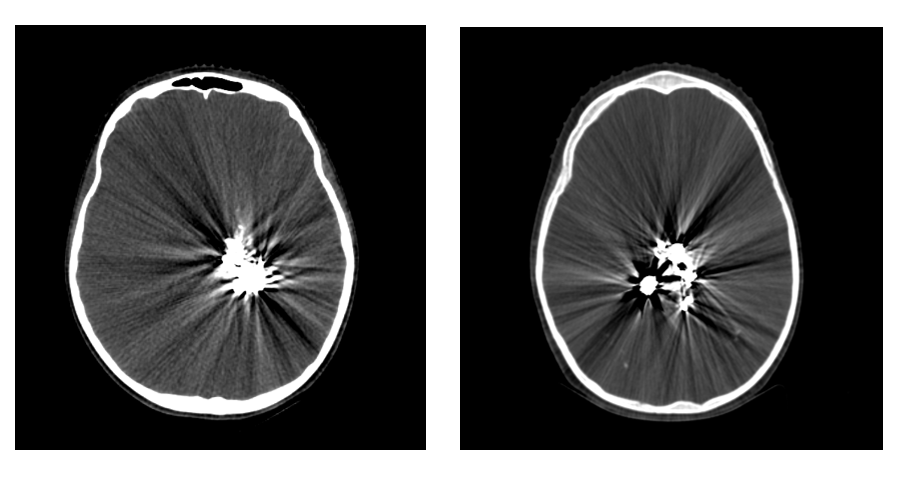

Refer to caption

Figure 3: Overall training pipeline. Step 1: random generation of high-density objects. Step 2: sinogram calculation for (a) input CT image an (b) generated objects. Step 3: removing parts of sinogram (a) using sinogram (b) as a binary mask. Step 4: the output of the inpainting model (the blue arrow highlights training input-output pairs). Step 5: inverse Radon transform of (4). Step 6: suppression of the residual artifacts by the image-to-image network (the orange arrow represents training data).

At steps 4 and 6 we use convolutional neural networks as described in Section II-C. To measure the effectiveness of the proposed algorithm in comparison with only sinogram inpainting and direct image to image model, we also trained the same pipeline without step 4 and step 6, respectively. More details on the pipeline and training loops can be found in Figure 3.